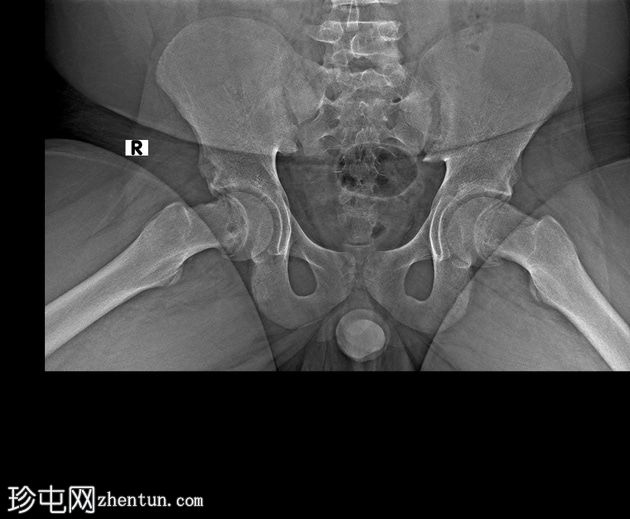

X线片

1.jpg

正位片

双侧股骨近端骨骺皮质不规则,轻度增宽。

双侧股骨骨骺轻度后内侧移位。